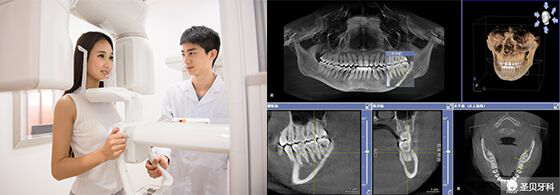

广州越秀圣贝口腔门诊部口腔的美颜正畸系统采用计算机辅助三维诊断、个性化设计以及数字化成型,智能控制每颗牙齿的移动,预测牙齿矫正后的位置,在矫治前用计算机模拟临床牙齿移动方式,让患者更清楚的感受矫正后的效果和所需要的时间,实现矫正模拟过程及结果的三维可视化。它根据面部特点进行个性化设计,通过改变牙齿排列关系、上下颌的咬合关系,以及牙列及牙槽骨的排列关系,解决颌骨、颅面的不协调,重塑美好颜面,达到面部整体的和谐美。